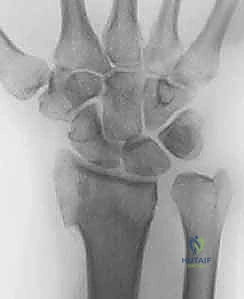

صورة طبية توضح كسر الناتئ الإبري

استخدام الأشعة السينية في التشخيص

1. الأشعة السينية (X-rays): بوضعيات متعددة (أمامية خلفية، وجانبية دقيقة). الوضعية الجانبية الحقيقية (True Lateral) حاسمة لاكتشاف أي خلع جزئي في المفصل (DRUJ).